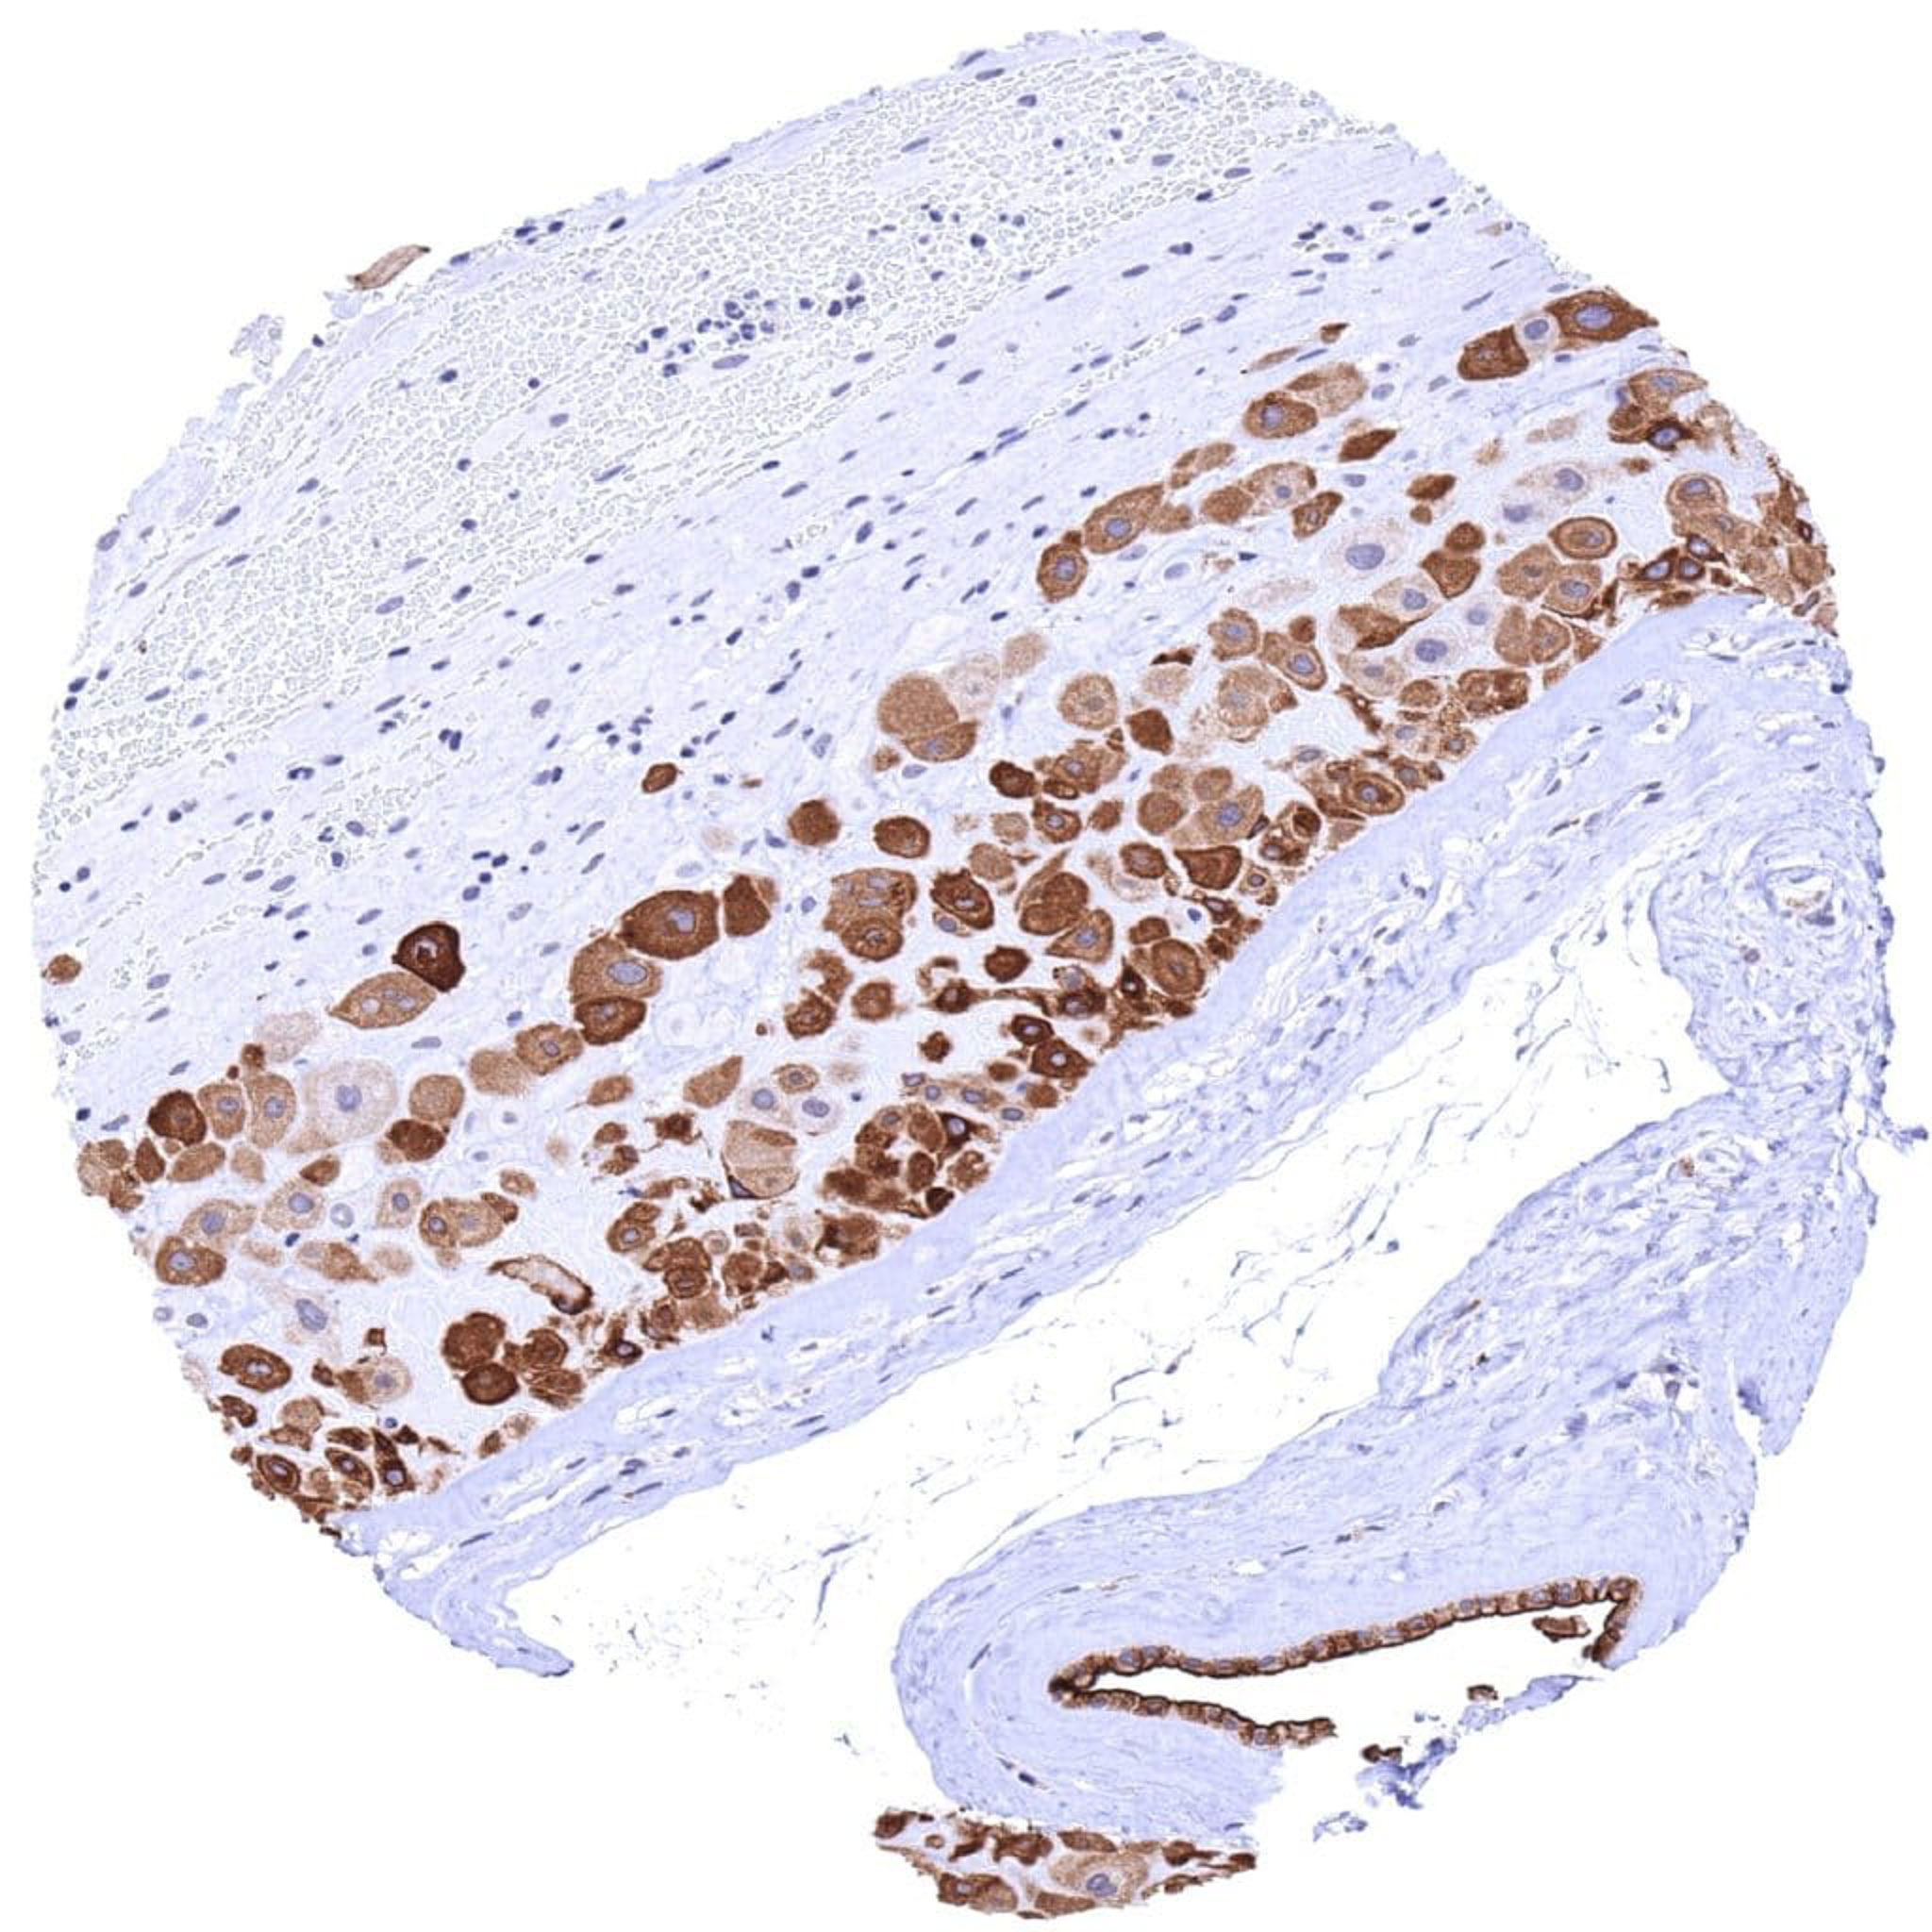

Placenta (amnion)- Strong UPK1B staining of all amnion cells

Placenta (amnion) – Strong UPK1B immunostaining in amnion cells of the placenta.

Placenta (chorion)- Strong cytoplasmic and membranous UPK1B staining of chorion cells